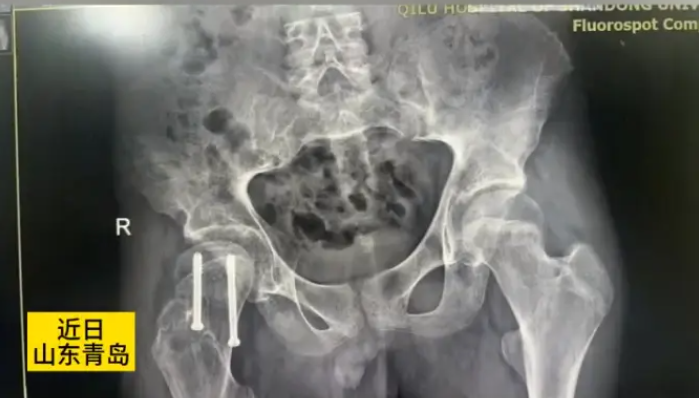

Bên cạnh hội chứng đứt cuống tuyến yên, anh Ai còn mắc chứng trượt đầu xương đùi, một bệnh thường gặp ở thanh thiếu niên. Chứng bệnh này làm tình trạng sức khỏe của anh thêm phức tạp, gây đau đớn và hạn chế vận động.

Trượt đầu trên xương đùi (SCFE) là một tình trạng thường gặp ở vùng hông, chủ yếu xuất hiện ở thanh thiếu niên và thanh niên trong giai đoạn phát triển thể chất. Ở bệnh lý này, cổ xương đùi bị trượt lệch khỏi vị trí bình thường trên đầu xương đùi, hướng lên trên và ra trước, gây đau đớn, cứng khớp và làm suy giảm độ ổn định của khớp háng. Tình trạng này thường tiến triển từ từ và có tỷ lệ mắc ở nam giới cao hơn so với nữ.

May mắn thay, anh Ai đã được phẫu thuật đóng đinh nội tủy rỗng để điều trị chứng trượt đầu xương đùi bên phải. Ca phẫu thuật đã thành công, giúp giảm đau đáng kể và cải thiện khả năng vận động cho anh. Tiên lượng sau phẫu thuật của anh được đánh giá là tốt.